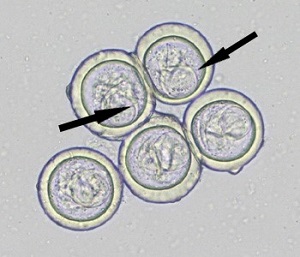

A 4-year-old boy went for a routine medical examination with his parents after they returned from a one-year sabbatical, studying primates in their natural habitat in central Africa. The child had no symptoms other than intermittent abdominal pain which started in the last four months of their stay in Africa. The parents reported seeing what appeared to be motile, rice grain-like objects in his stool recently. A stool sample was collected and processed for routine ova and parasite (O&P) examination. Figures A and B show what the technologist observed in the microscopic examination of the stool concentrate at 40x and 100x respectively. The objects measured 45-47 µm in diameter. What is your diagnosis? Based on what criteria?

Figure A

Figure B